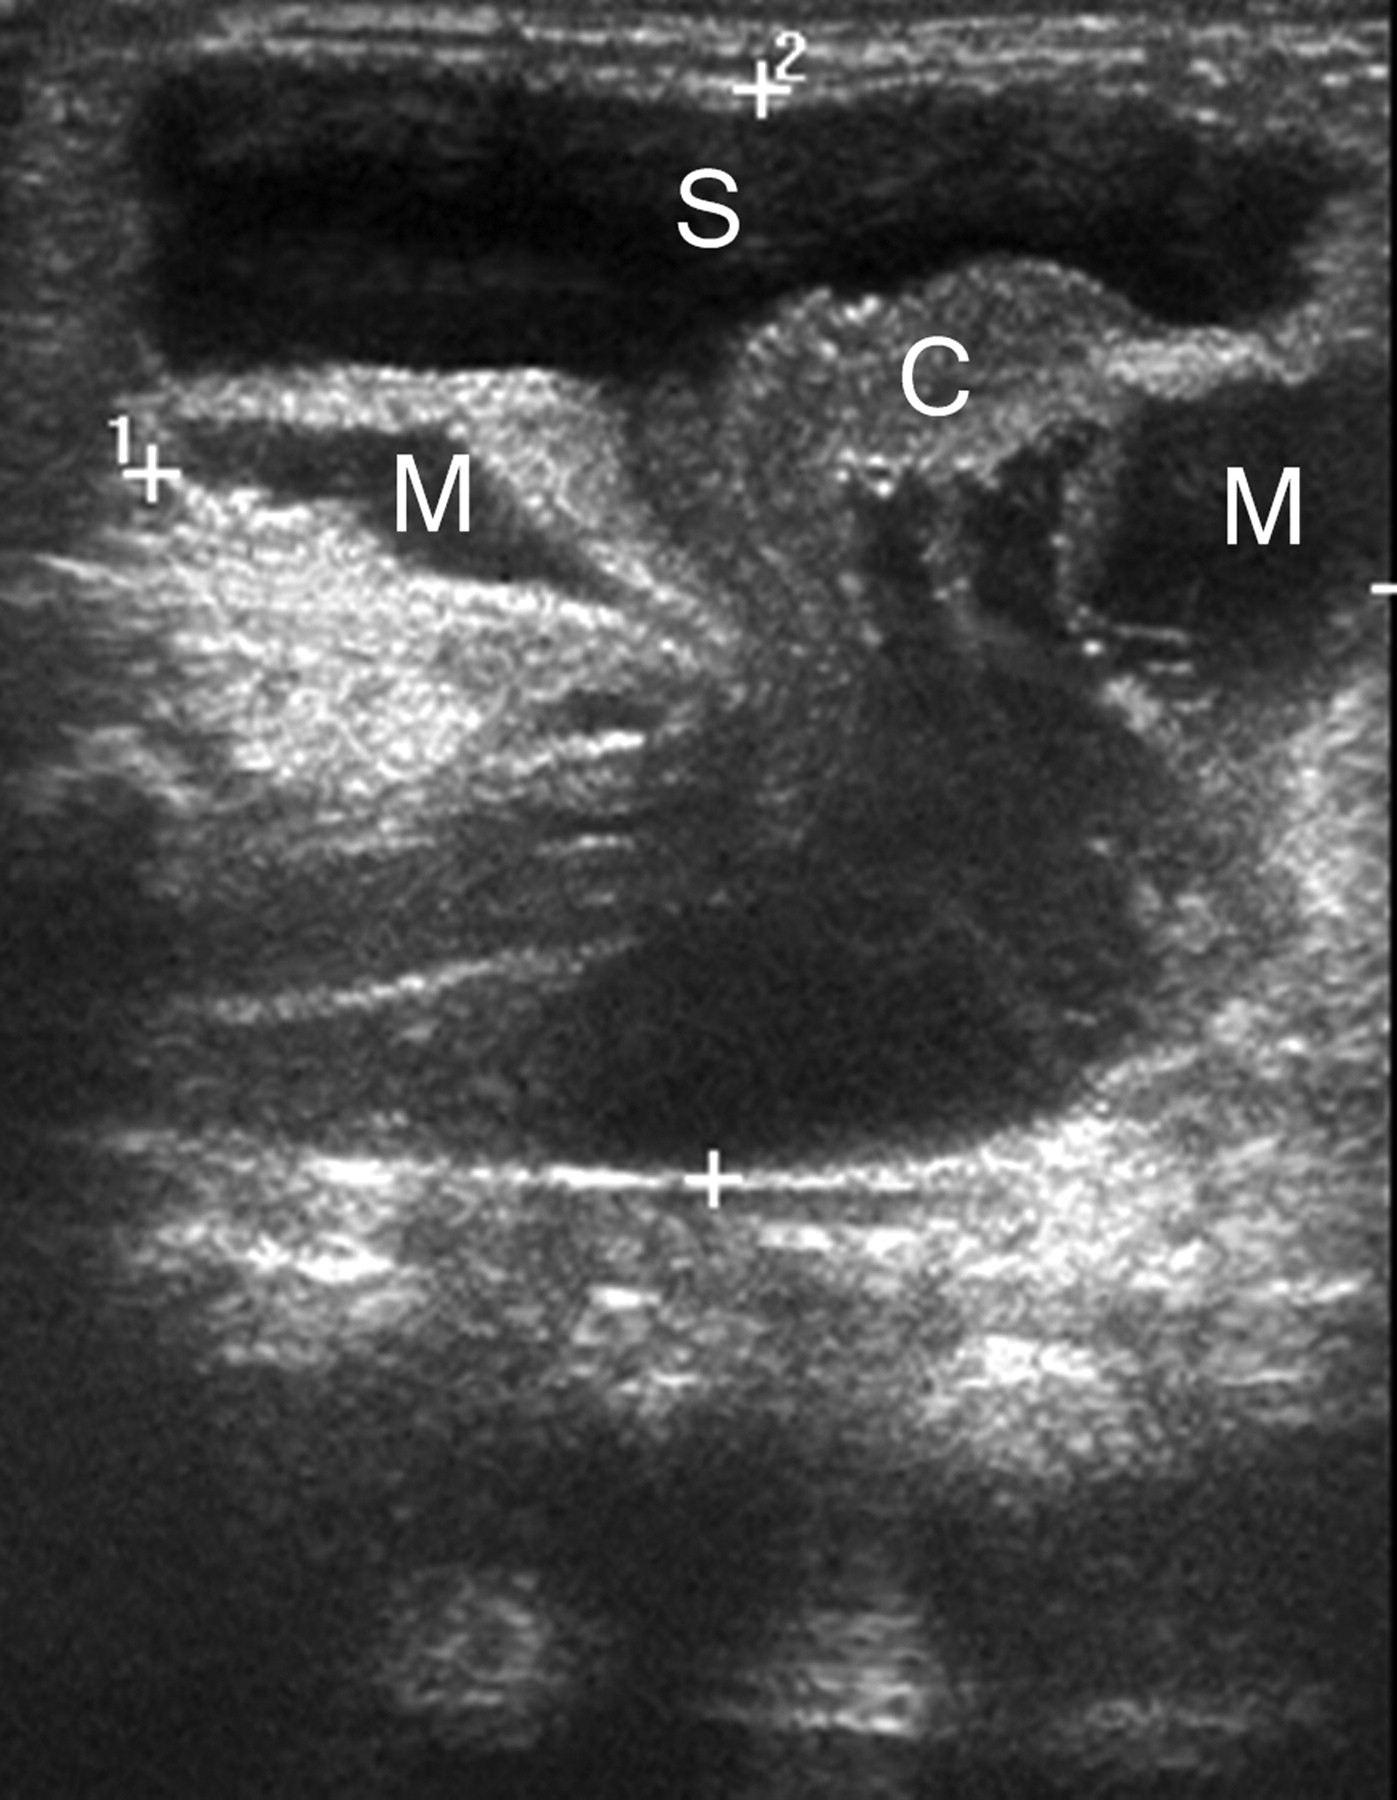

一个已经男孩看到一个突出的无痛性软质量(8×7厘米)在出生后骶区,与完整的皮肤覆盖。超声显示囊性扩张的远端中央管周围扩张蛛网膜下腔(图1)。MRI证实的诊断终端脊髓囊肿状突出的典型发现trumpetlike扩口syringocele和脑脊髓膜突出(图2)。

轴向t1 (A)和t2加权磁共振扫描显示类似的描述(B)作为超声。箭头指向变形和流离失所的脊髓。M =脑脊髓膜突出;S = syringocele;Vb =椎体。

终端脊髓囊肿状突出,一种罕见的神秘脊柱闭合不全,特点是hydromyelic扩张的远端中央管(syringocele),通过后脊柱裂膨胀,扩大包围硬铝护套(脑脊髓膜突出)。1虽然少见,但应列入鉴别诊断先天性骶骨质量。虽然超声波是一个很好的初步筛查模式,MRI是必要的证实了解剖学诊断和描述。2